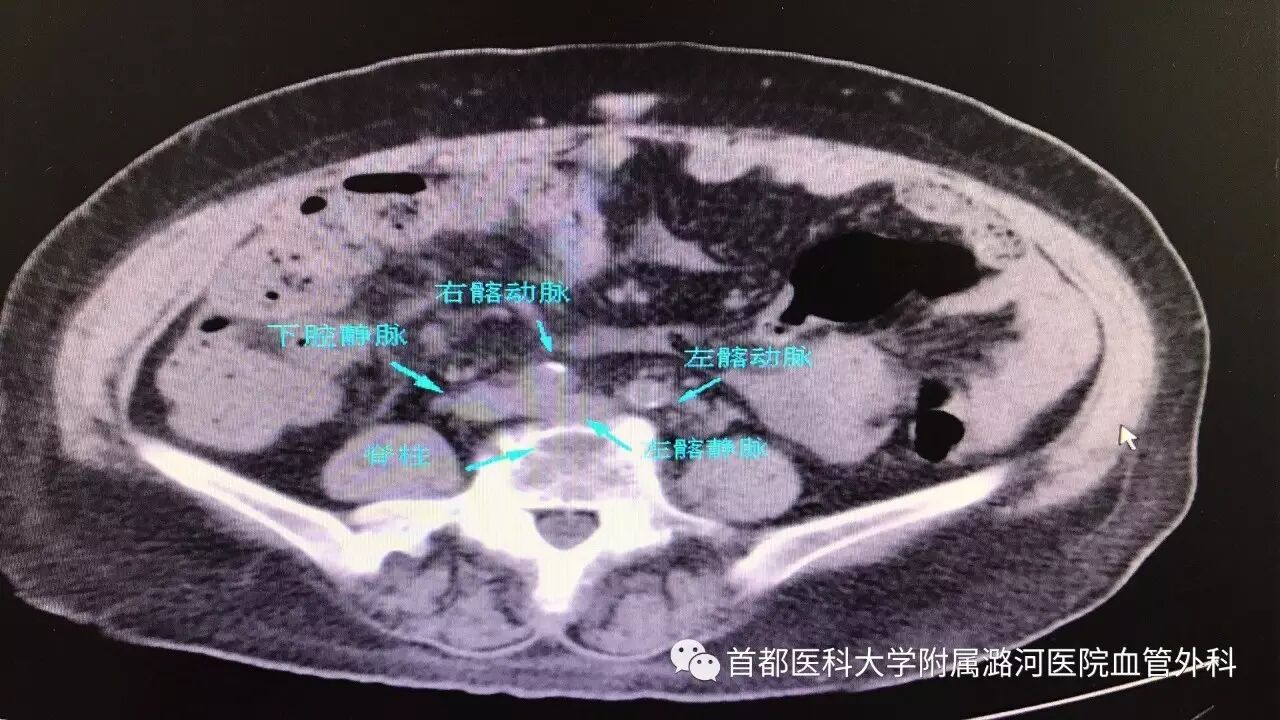

下肢CTV

下肢静脉CTV:

下腹部平扫也能初步判断有没有左髂静脉压迫,对于怀疑该疾病的可以常规检查下腹平扫CT。